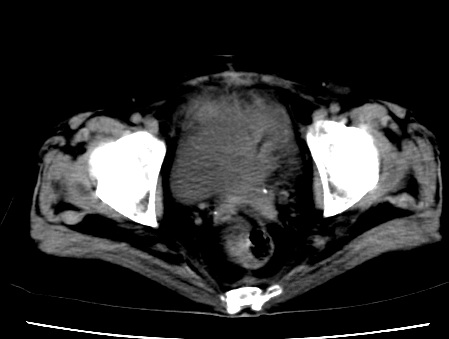

标题: CT23975:女61岁,腹部不适,明显消瘦 [打印本页]

标题: CT23975:女61岁,腹部不适,明显消瘦

既往5年前卵巢癌行子宫及附件切除,右乳癌术后一年,考虑腹膜转移?

大量腹水,考虑腹膜转移。肝脏低密度灶。1囊肿,2转移。

1)结合病史,考虑腹膜及网膜转移瘤。2)肝脏多发性低密度灶,不排除转移瘤。3)大量腹水。

考虑卵巢癌行子宫术后复发,并肝、腹腔 、大网膜转移可能性大。

大量腹水。